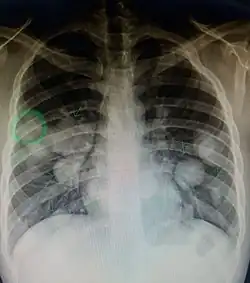

- Lung metastasis: cough, hemoptysis and dyspnea[10] (shortness of breath)

Metastatic tumors are very common in the late stages of cancer. The spread of metastasis may occur via the blood or the lymphatics or through both routes. The most common sites of metastases are the lungs, liver, brain, and the bones.[10]

CT image of a lung metastasis

CT image of a lung metastasis -

Metastatic cancer in the lungs

Metastatic cancer in the lungs -